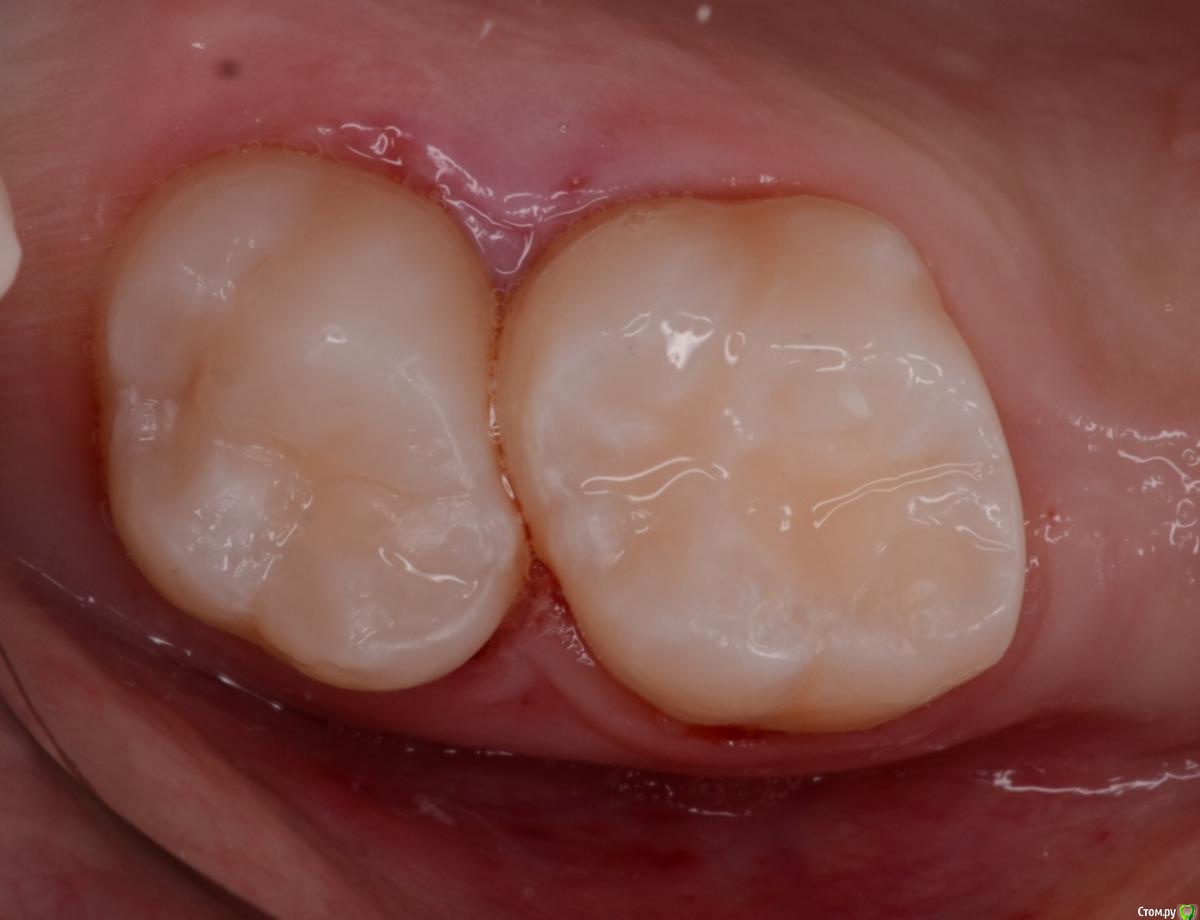

CRAZYDUCK Опубликовано 30 мая, 2018 Автор Поделиться Опубликовано 30 мая, 2018 (изменено) В этом случае немного видно преп под коронку . Описание случая ниже .B9CDEEE8-69F9-4F9D-B72C-1663ADE5EECD.bmp Изменено 30 мая, 2018 пользователем CRAZYDUCK 7 Ссылка на комментарий

CRAZYDUCK Опубликовано 30 мая, 2018 Автор Поделиться Опубликовано 30 мая, 2018 Лечение 7.4 . Необратимый пульпит 7.4 зуба . В данном случае хорошо видно , что после ампутации гемостаз не наступает ( полость зуба заполнена кровью). Позже выложу случай со спонтанным гемостазом . Одного критерия , который бы со 100% вероятностью помогал понять , что нужна экстирпация нет . ❗Жалобы —если была самопроизвольная боль , которая не была связана с приемом пищи или выраженное последействие после пищи, боль купировалась приемом обезболивающего . Болит так , что ребёнок плачет . Самопроизвольная боль есть - скорее всего экстирпация ( если не удаление зуба).❗RVG если полость пульпы сообщается с кариозной полостью , то скорее всего экстирпация - учитывать проекцию тоже нужно .❗Гемостаз должен наступить через 4-5 минут после ампутации, если его нет - экстирпация .В данном случае боль была только кратковременная после приёма жесткой пищи . Преп, экстирпация ( Sxмашинный протейпер ), потом до 25.02 ручными , гипохлорит 3%, Йодотин в каналы , IRM культя , коронка фиксирована на Айрекс Цем . Обратите внимание - во время обработки зуба под Коронку - все в хлам и платок и десна . Предупреждаем родителей о дискомфорте , связанном с травмированием десны. 7 Ссылка на комментарий